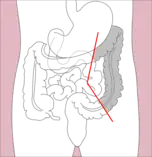

- Right hemicolectomy and left hemicolectomy refer to the resection of the ascending colon (right) and the descending colon (left), respectively. When part of the transverse colon is also resected, it may be referred to as an extended hemicolectomy.[5]

Right hemicolectomy

Right hemicolectomy Right extended hemicolectomy

Right extended hemicolectomy Left hemicolectomy

Left hemicolectomy Extended left hemicolectomy

Extended left hemicolectomy - Transverse colectomy is also possible, though uncommon.